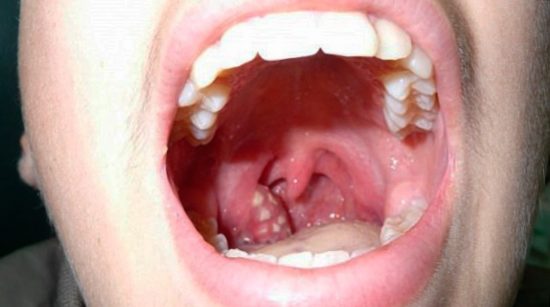

Розпізнати ознаки хвороби не так складно, так як вони виражені найчастіше виразками, нальотами і ерозією на слизових поверхнях ротової порожнини. При ангіні такого виду у пацієнта діагностується виразковими покриттями на мигдалинах.

Стоматитная ангіна розвивається на всіх поверхні епітелію рота і горла одночасно. На виразкових наростах з’являється білуватий або жовтий наліт. Якщо пацієнт вирішить самостійно видалити плівку з пошкодженої тканини, виразка відкриється, що дуже небезпечно, інфікуванням прилеглих органів.

Симптоми стоматитной ангіни: наліт, виразки на слизовій оболонці мигдаликів.

На ерозіях з’являється наліт білого або жовтого кольору. Під плівкою на уражених тканинах утворюються виразки. Гострий тонзиліт протікає важко, особливо у дитини. У хворого піднімається температура тіла, проковтування їжі і напоїв викликає хворобливі відчуття, з’являється підвищене слиновиділення.

Фото 3. Сама ангіна розташована в горлі, запалення утворюються і гнійнички, які викликають температуру і сильний біль у горлі.